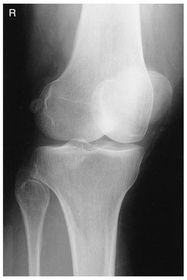

A. medial and lateral intercondylar tubercles B. lateral epicondyle femur C. lateral condyle femur D. lateral condyle tibia E. articular facets tibia (tibial plateau) F. medial condyle tibia G. medial condyle femur H. medial epicondyle femur I. patella

AP Medial Oblique Knee pt supine w/ knee rotated medially 45 degrees - CR parallel to tibial plateau @ 1/2 in distal to apex of patella *will see LATERAL condyles best along with the APEX OF FIBULA*

AP Lateral Oblique Knee pt supine w/ knee rotated externally 45 degrees - CR parallel to tibial plateau @ 1/2 in distal to apex of patella * will see MEDIAL condyles best along with 1/2 of patella free of superimposition of the condyles*